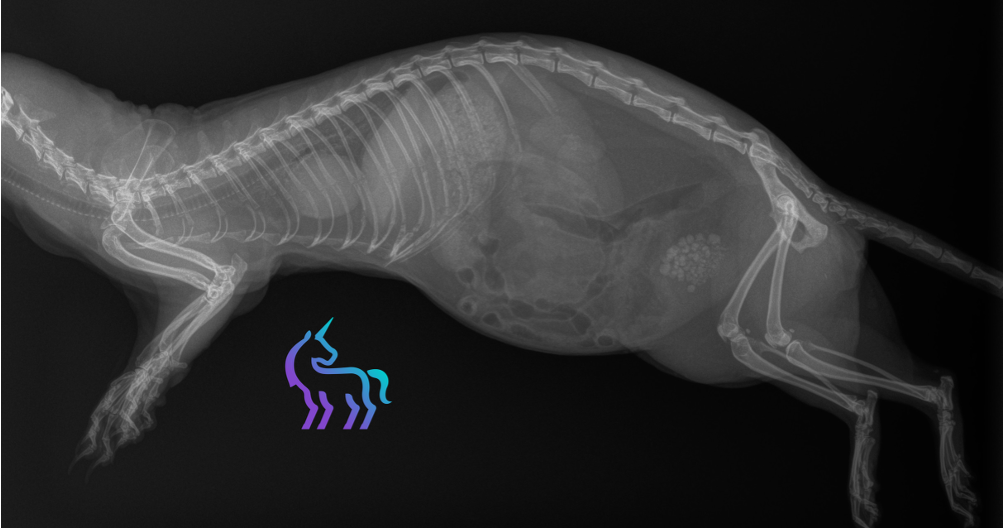

Échographie abdominale

Une échographie est réalisée afin d’évaluer l’extension des lésions et l’état des reins. Les reins apparaissent sans anomalie structurelle.